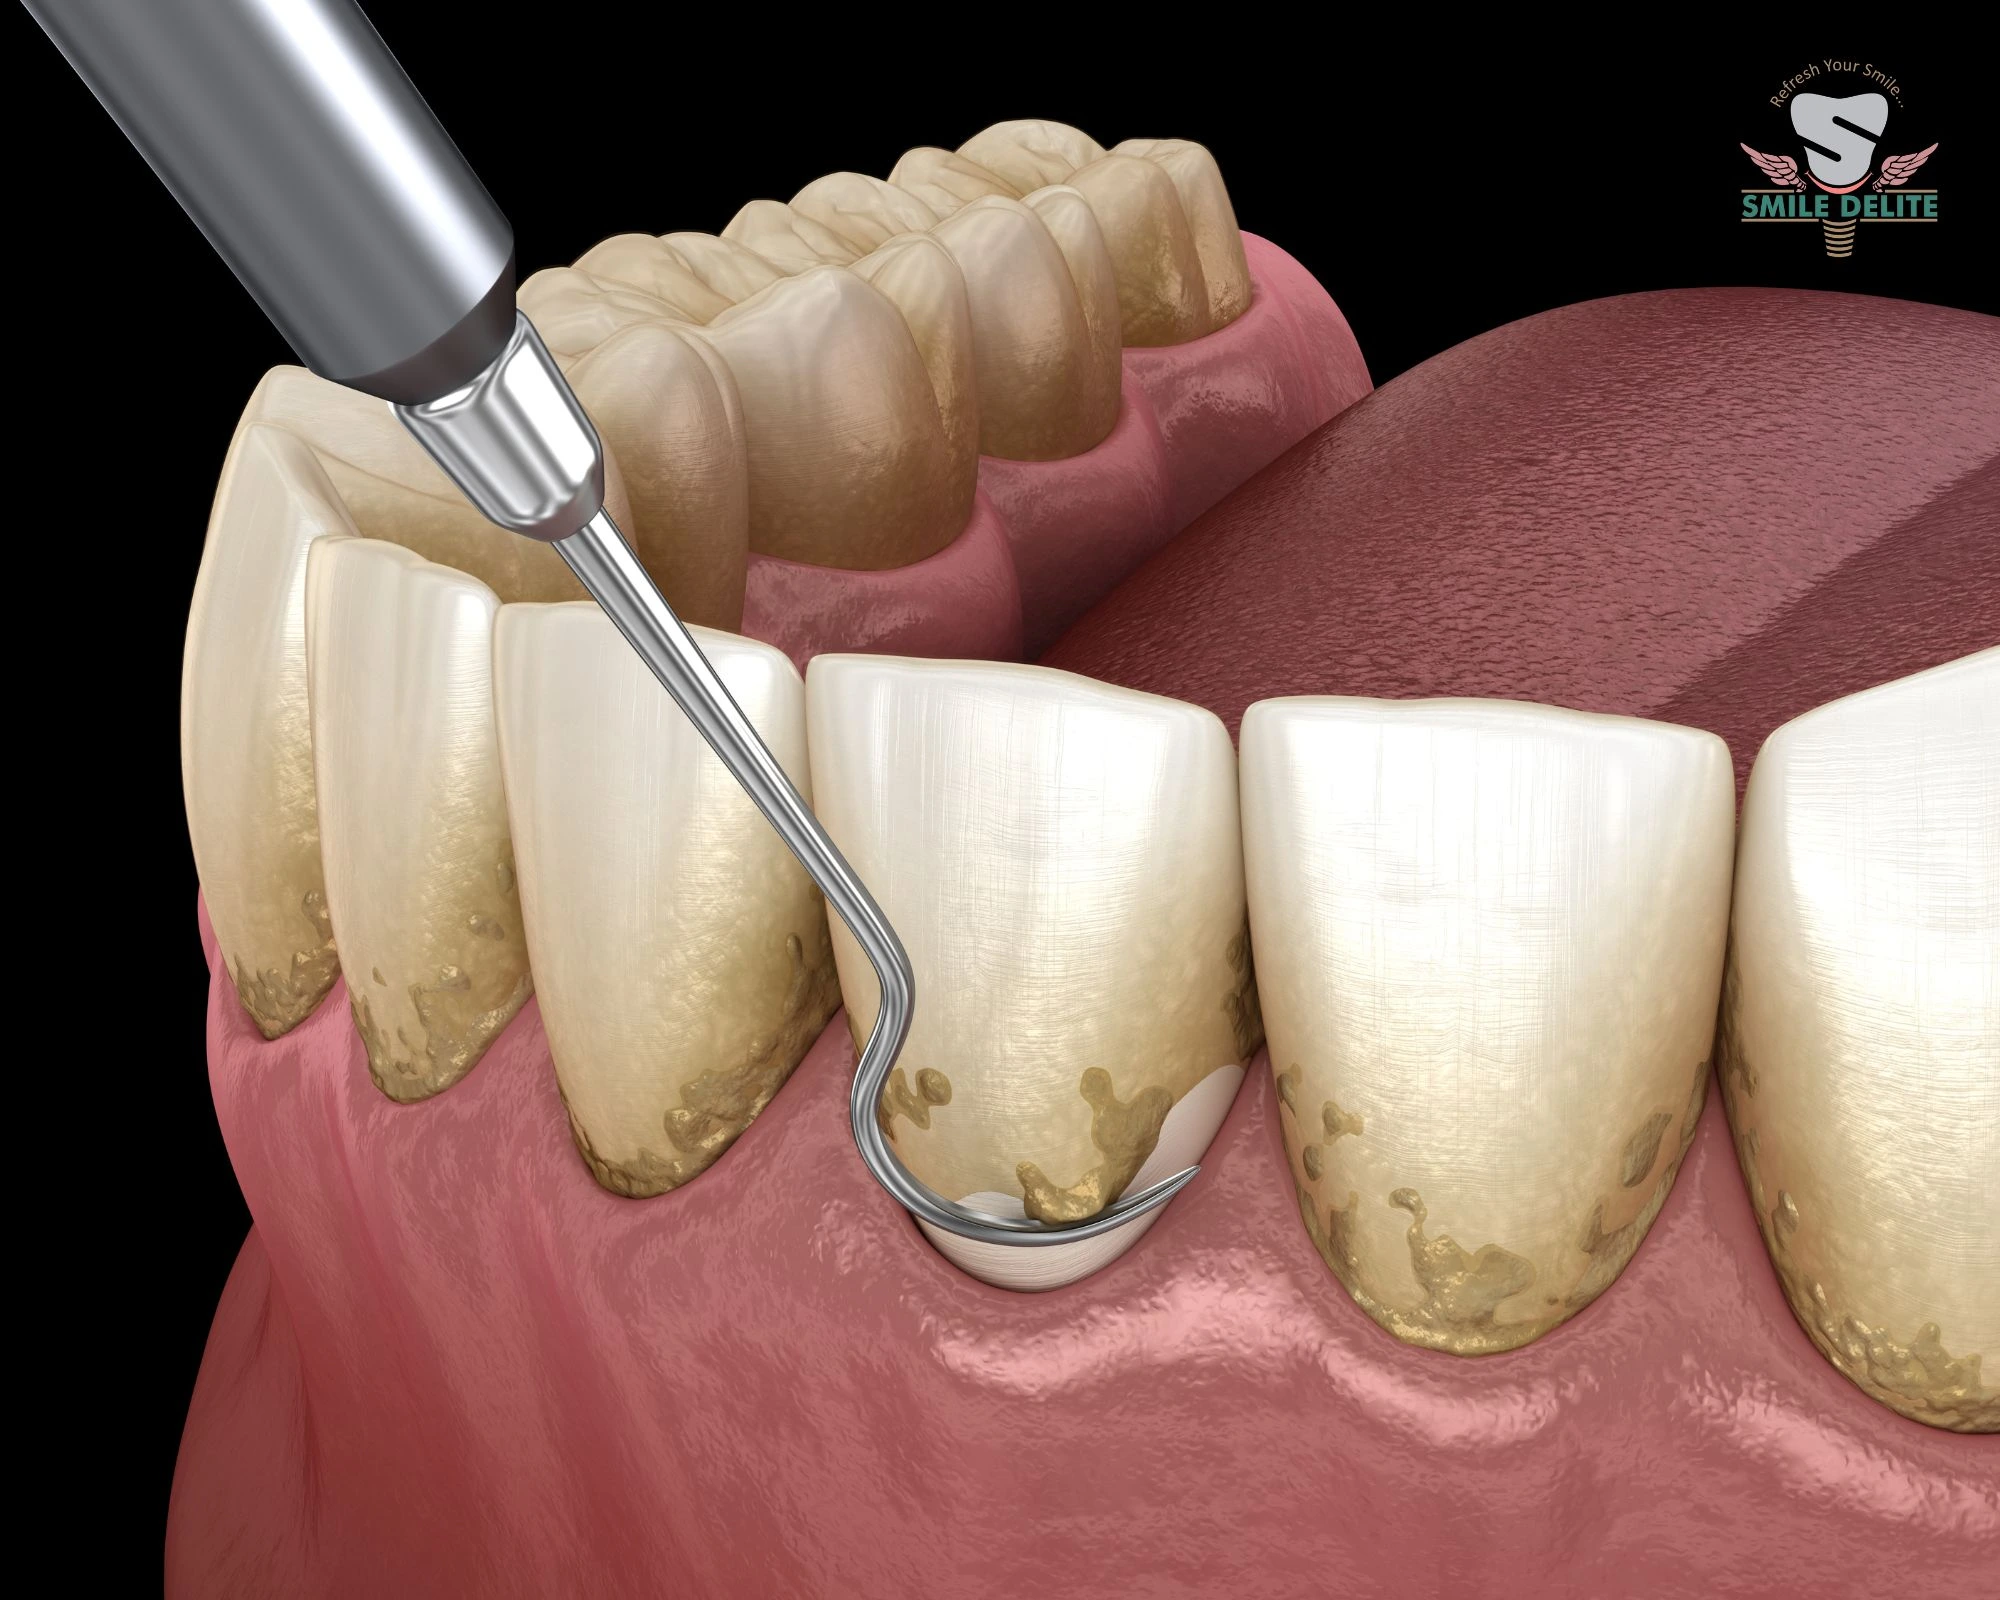

In-house digital imaging for accurate diagnosis and treatment planning.

Yes. SMILE D’ELITE has in-house OPG and CBCT imaging for accurate diagnosis and advanced treatment planning.